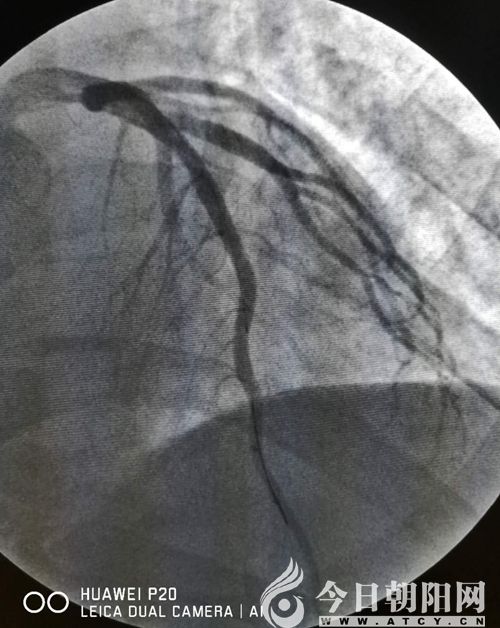

趙某術(shù)前

趙某術(shù)后

緊接著,來(lái)不及松上一口氣的胸痛中心團(tuán)隊(duì)又開(kāi)始為患者趙某實(shí)施手術(shù)。該患者冠脈前降支近段100%閉塞,單爽為其實(shí)施球囊擴(kuò)張術(shù),并植入支架一枚,患者胸痛得以緩解。